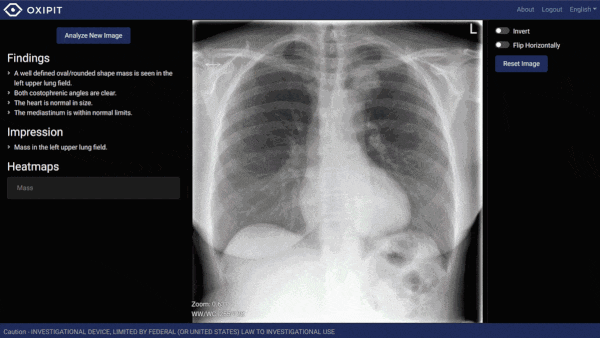

AI system recognizes normal chest x-rays

AI Enters the Radiology Department: ChestLink, an AI X-Ray Tool Approved by European Officials

The European Union approved for clinical use an AI system that recognizes normal chest X-rays. ChestLink is the first autonomous computer vision system to earn the European Economic Area’s CE mark for medical devices...